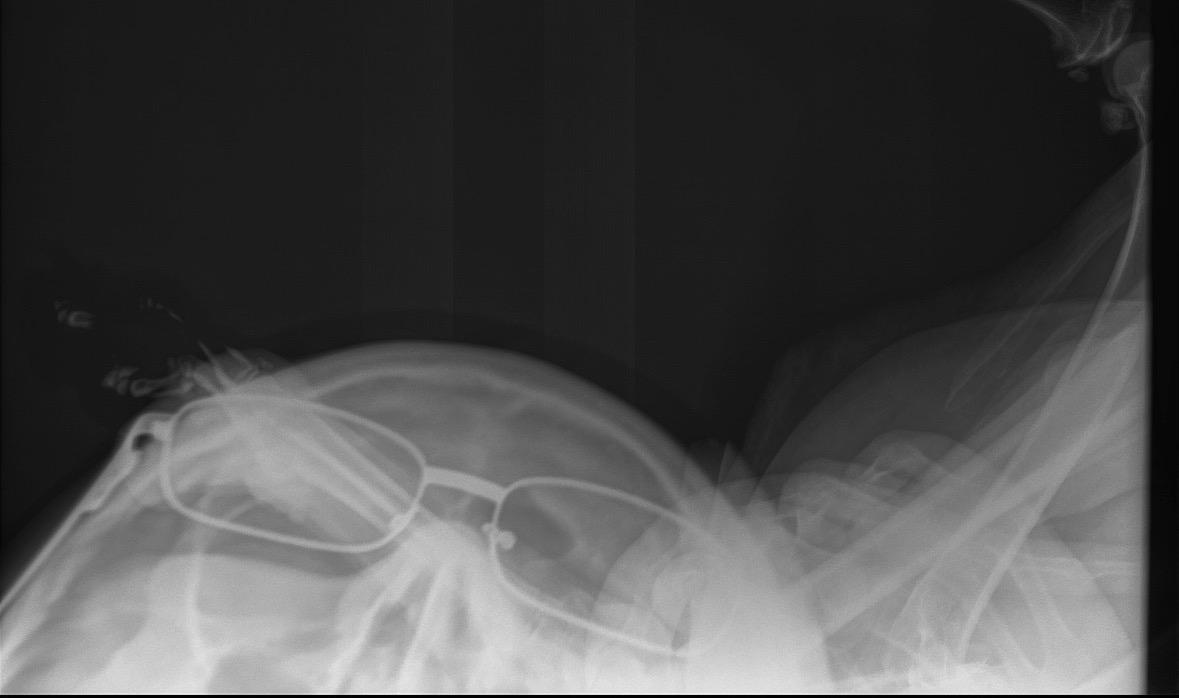

Sage Radiation Safety – Texas is a practical, self-paced certification course for veterinary technicians and veterinarians who operate or assist with X-ray and CT equipment. Designed for real-world clinical use, this course covers radiation biology, cumulative exposure risk, deterministic vs stochastic effects, and the core principles of time, distance, and shielding. You’ll learn how technique choices (kVp, mAs, collimation, positioning) directly impact dose, image quality, and repeat rates. The program also reviews equipment terminology, workflow expectations, dosimetry, PPE use, and essential Texas compliance requirements. With video lessons, knowledge checks, and a final exam, this course provides clear, actionable training to help you reduce exposure, avoid costly mistakes, and protect yourself, your team, and your patients. Participants who pass a 50 question multiple choice final test will receive a certificate of completion and 3 hours of RACE-approved CE.